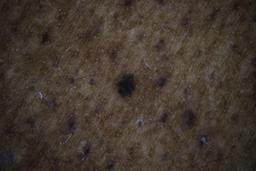

ISIC_6598546

Clinical

| Field | Value |

|---|---|

| age_approx | 60 |

| anatom_site_1 | Trunk |

| anatom_site_2 | Posterior trunk |

| concomitant_biopsy | False |

| dermoscopic_type | contact polarized |

| diagnosis_1 | Benign |

| diagnosis_confirm_type | single contributor clinical assessment |

| fitzpatrick_skin_type | VI |

| image_manipulation | instrument only |

| image_type | dermoscopic |

| lesion_id | IL_6711989 |

| patient_id | IP_8590441 |

| sex | male |